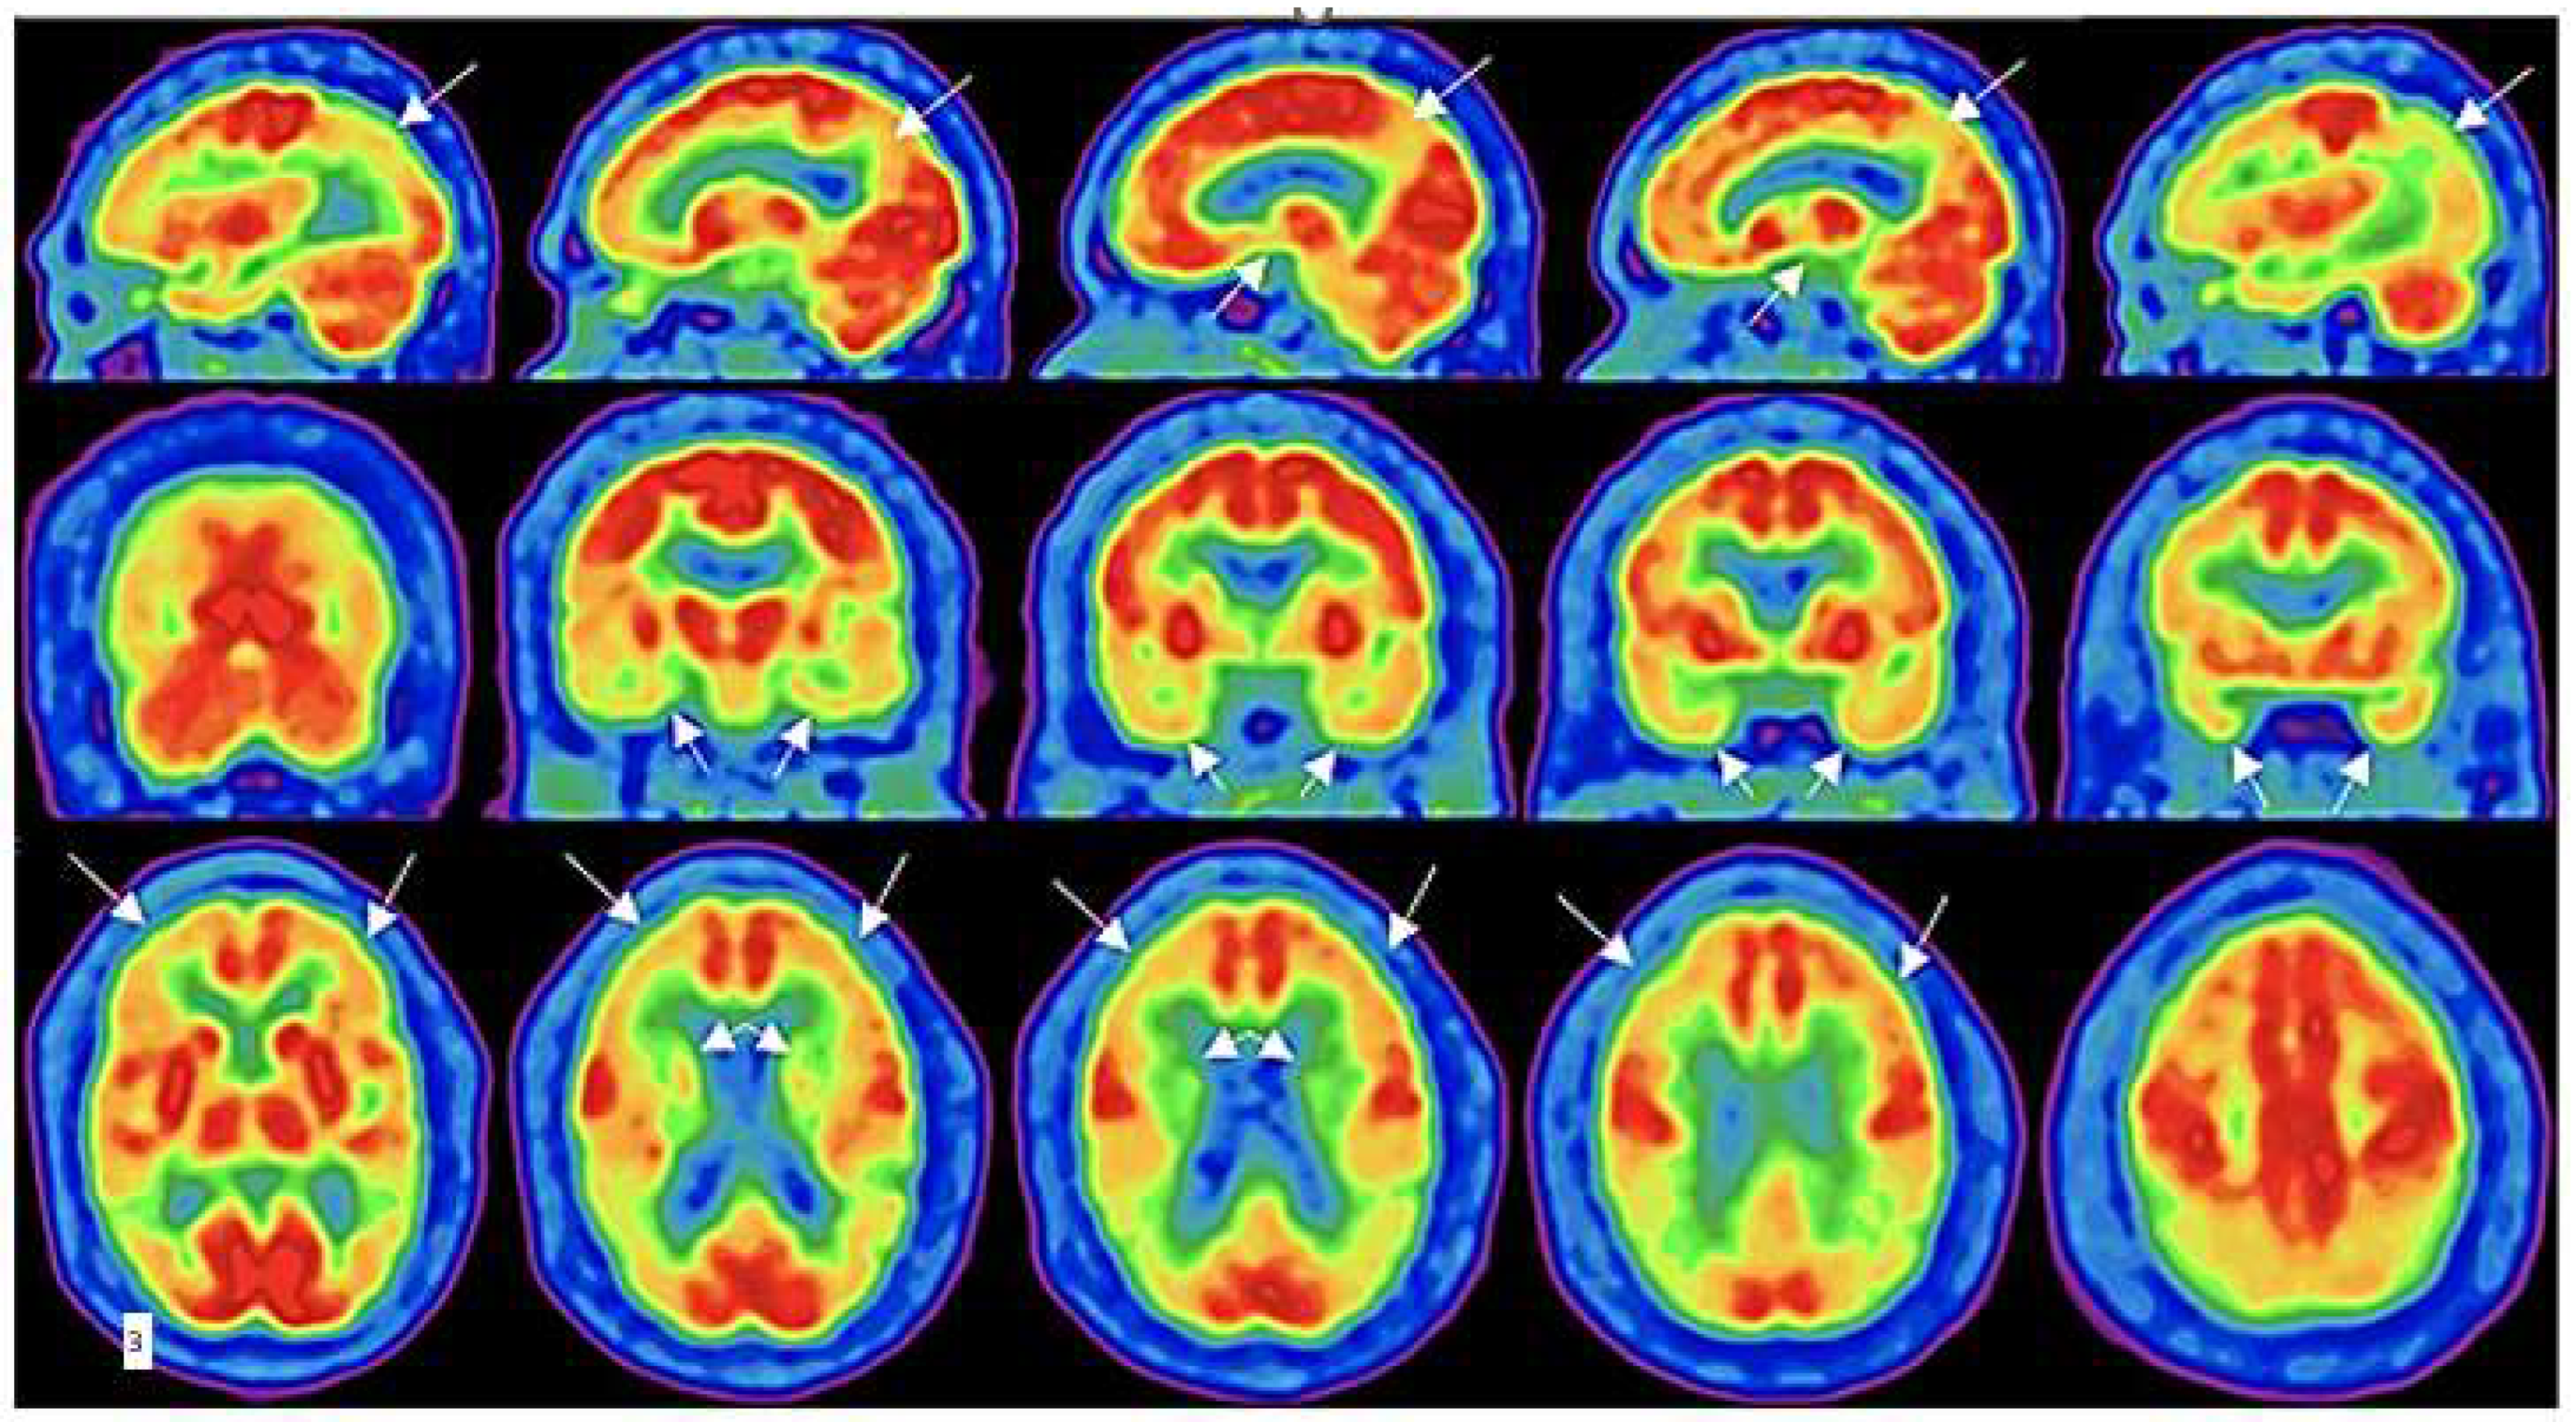

- Hattori, N.; Huang, S.-C.; Wu, H.-M.; Liao, W.; Glenn, T.C.; Vespa, P.M.; E Phelps, M.; A Hovda, D.; Bergsneider, M. Acute changes in regional cerebral (18)F-FDG kinetics in patients with traumatic brain injury. . 2004, 45, 775–83. [Google Scholar]

- Wu, H.-M.; Huang, S.-C.; Hattori, N.; Glenn, T.C.; Vespa, P.M.; Yu, C.-L.; Hovda, D.A.; Phelps, M.E.; Bergsneider, M. Selective Metabolic Reduction in Gray Matter Acutely following Human Traumatic Brain Injury. J. Neurotrauma 2004, 21, 149–161. [Google Scholar] [CrossRef]

- Bergsneider, M.; Hovda, D.A.; Shalmon, E.; Kelly, D.F.; Vespa, P.M.; Martin, N.A.; Phelps, M.E.; McArthur, D.L.; Caron, M.J.; Kraus, J.F.; et al. Cerebral hyperglycolysis following severe traumatic brain injury in humans: a positron emission tomography study. J. Neurosurg. 1997, 86, 241–251. [Google Scholar] [CrossRef]

- Worley, G.; Hoffman, J.M.; Paine, S.S.; Kalman, S.L.; Claerhout, S.J.; Boyko, O.B.; Kandt, R.S.; Santos, C.C.; Hanson, M.W.; Oakes, W.J.; et al. 18-FLUORODEOXYGLUCOSE POSITRON EMISSION TOMOGRAPHY IN CHILDREN AND ADOLESCENTS WITH TRAUMATIC BRAIN INJURY. Dev. Med. Child Neurol. 1995, 37, 213–220. [Google Scholar] [CrossRef]

- Bergsneider, M.; Hovda, D.A.; Lee, S.M.; Kelly, D.F.; McARTHUR, D.L.; Vespa, P.M.; Lee, J.H.; Huang, S.-C.; Martin, N.A.; Phelps, M.E.; et al. Dissociation of Cerebral Glucose Metabolism and Level of Consciousness During the Period of Metabolic Depression Following Human Traumatic Brain Injury. J. Neurotrauma 2000, 17, 389–401. [Google Scholar] [CrossRef]

- Komura, A.; Kawasaki, T.; Yamada, Y.; Uzuyama, S.; Asano, Y.; Shinoda, J. Cerebral Glucose Metabolism in Patients with Chronic Mental and Cognitive Sequelae after a Single Blunt Mild Traumatic Brain Injury without Visible Brain Lesions. J. Neurotrauma 2019, 36, 641–649. [Google Scholar] [CrossRef]